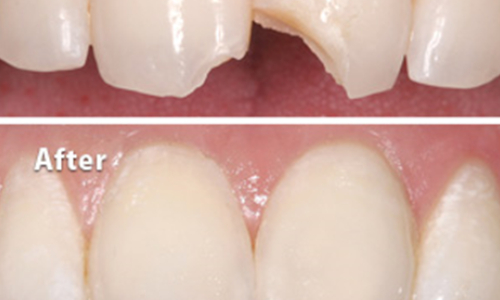

Modern dentistry has introduced various tooth colored materials which are used for treatments like tooth decay, tooth fracture, diastema closure, smile designing.

Fractured tooth segment